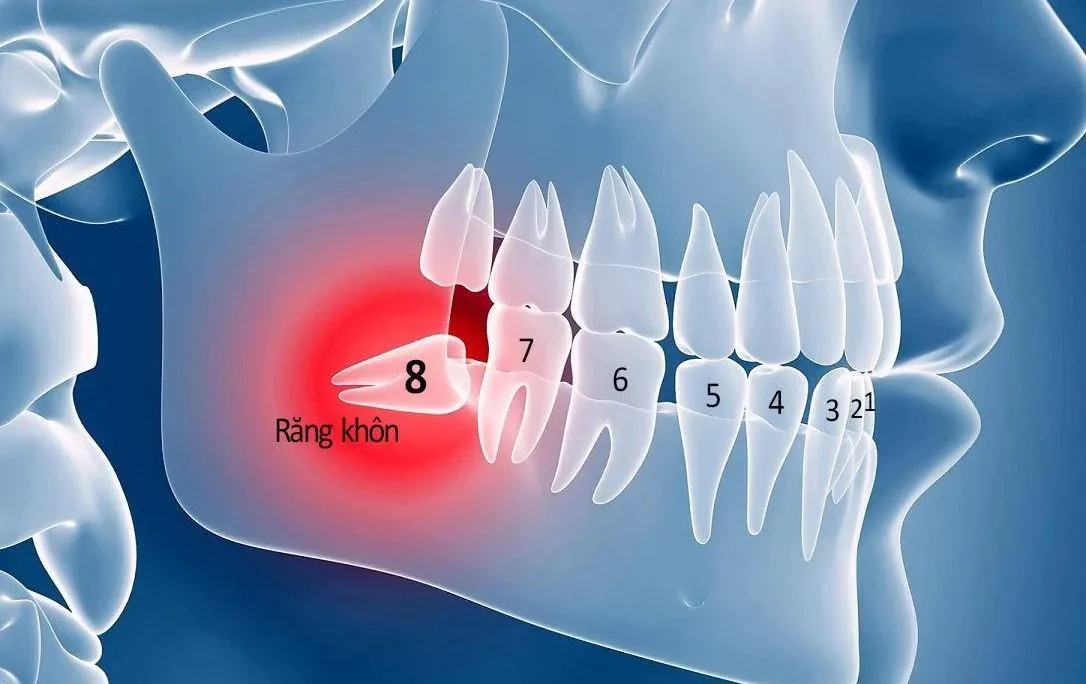

Viêm nha chu mãn tính

Sau thời gian dài tích tụ, mảng bám trên răng ngày càng dày và cứng, ẩn chứa rất nhiều vi khuẩn gây bệnh, hay còn gọi là cao răng. Cao răng này dính chặt vào chân răng và nướu, làm tổn thương và phá huỷ khu vực quanh chân răng. Muốn lấy cao răng phải tới nha sĩ để điều trị.

Bệnh nha chu thường tiến triển chậm, nha chu mãn tính thường xảy ra ở độ tuổi trên 45 tuổi. Do đó, để phòng tránh căn bệnh này bạn chỉ cần chăm sóc răng đúng cách ngay từ hôm nay, khám răng định kỳ hàng năm và lấy cao răng.

Bệnh đang ở giai đoạn nặng hơn, bệnh tiến triển rất nhanh khiến người bệnh đau nhức liên tục, ăn uống khó chịu. Nếu không điều trị kịp thời, bệnh có thể gây mất răng, điều trị rất tốn kém.